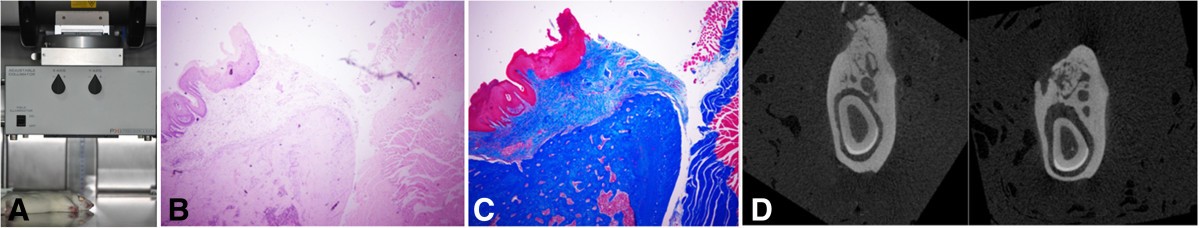

Figure 4

An experimental osteoradionecrosis rat model, including the apparatus with irradiation (A), and hematoxylin-eosin (B) and toluidine blue (C) staining with micro-computed tomogram views (D).